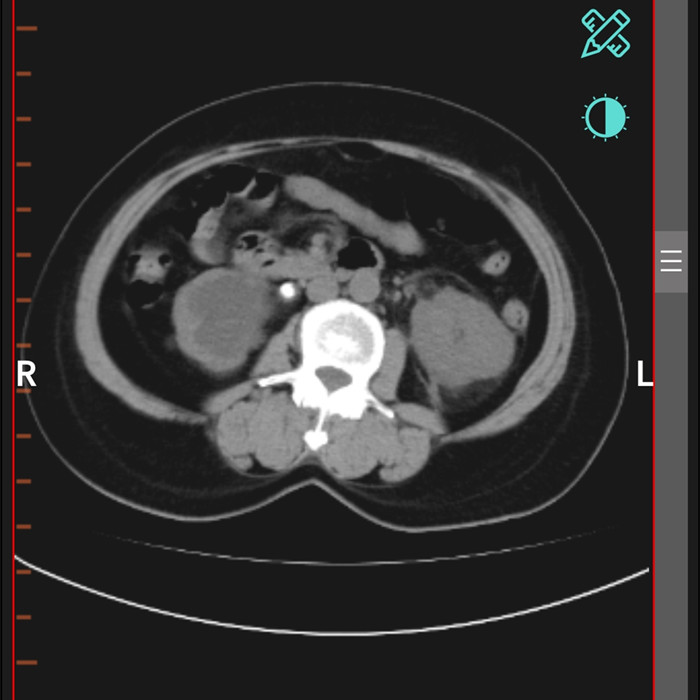

柴女士,62歲,北川縣擂鼓鎮(zhèn)人,因腰右側(cè)疼痛難忍,她來到北川羌族自治縣人民醫(yī)院就診,經(jīng)檢查提示,柴女士右輸尿管上段結(jié)石嵌頓引起重度腎積水。

“要及時解除梗阻,可以行腹腔鏡輸尿管切開取石術(shù)取代開放手術(shù)?!痹谥靹τ碌膸ьI(lǐng)下,這支剛剛成立的“泌尿外科團隊”,僅用了一個半小時就完成了手術(shù)。“腹腔鏡輸尿管切開取石術(shù)創(chuàng)傷小,患者腰腹部只有3個戳孔,術(shù)后恢復(fù)快?!敝靹τ抡f。